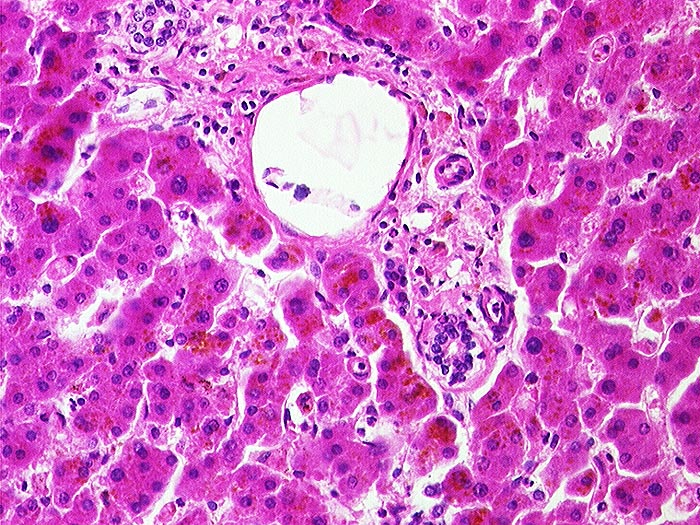

AP/ Leber bei Phenacetinabusus

Leber bei Phenacetinabusus

Artefakt / Fremdkörper / Pigment

Leber, Gallenwege, Pankreas

Leber

Leber HE